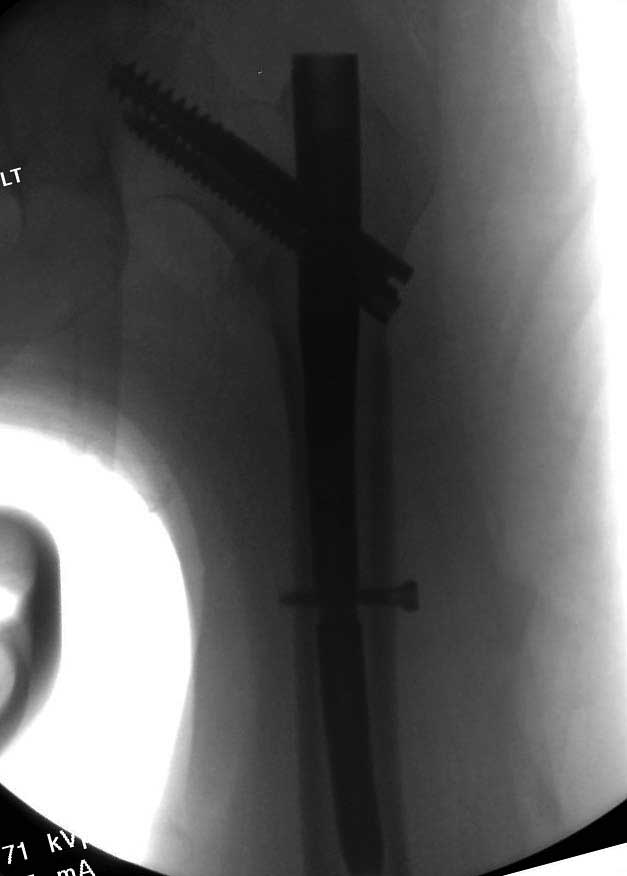

При таком переломе мы бы тоже поставили вертельный гвоздь - на следующий день встать и побежать - чем не перспектива? На прямом снимке винт стоит замечательно, а коварный аксиальный подкачал, хотелось бы больше по центру шейки и головки завести. Да и смещение, какое-никакое, но есть. Посему - нагрузка 15 кг, а расширяли бы не раньше, чем через 5 недель.

Прилагаю снимок сделанный еще в стационаре через 2 недели после операции.

Первые снимки показывают технические погрешности установки DHS. Не была достигнута репозиция, конечность в флексии и шейка в ротации. Сегодня все меньше обращают внимание на параметры для оценки репозиции (S контуры Lowell в обеих проекциях и Garden Alignment Index, в норме 155 и 180 градусов), хотя такие простые тесты помогли бы дорепонировать смещение. Винт находится сзади в головке, что при нагрузке поменяет вектор и вместо компрессии в линии перелома срежет головку-Cut Out!

В зависимости от дистанции линии перелома и латерального кортекса надо использовать разной длины barrel, т.е. конец баррели не должен доходить до пределов перелома. Здесь конец длинного ствола упирается в медиальный фрагмент, что мешает созданию компрессии, а более короткий barrel создал бы запас для компрессии. В боковой пластине вместо 4х можно было ограничится двумя шурупами, потому что головка шурупа в 4.5 мм выдерживает давление до 350 кг.